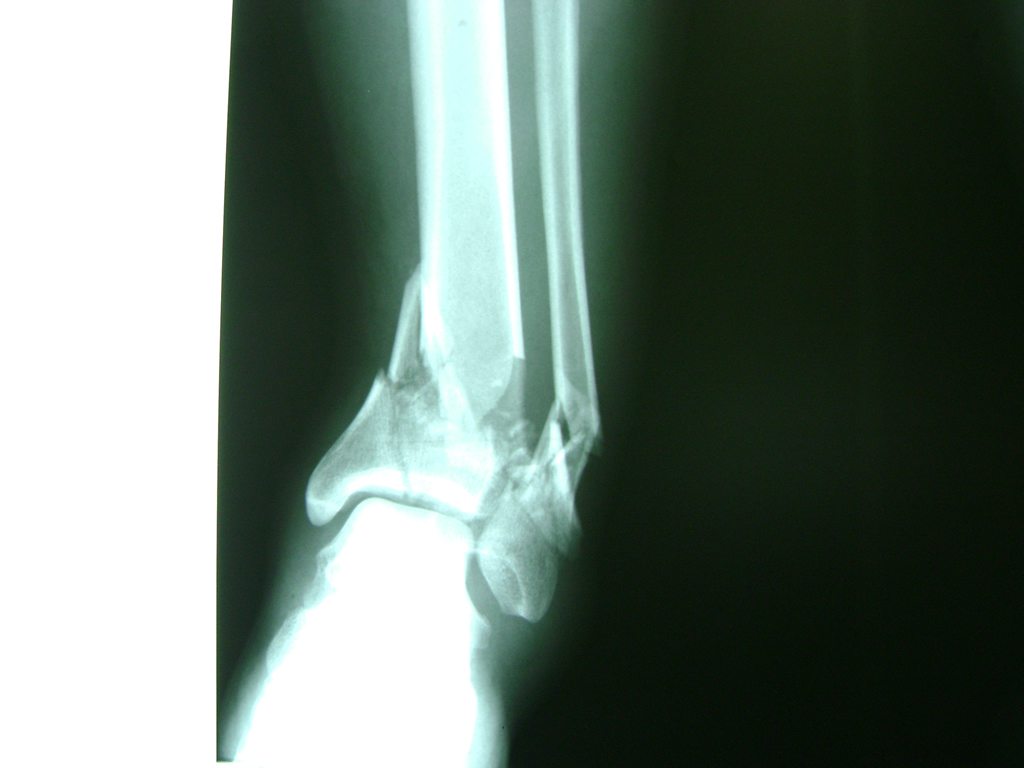

Una fractura de tobillo es la rotura de uno o más de los huesos del tobillo. Estas fracturas pueden ser:

- Parciales (el hueso está sólo parcialmente fisurado, no del todo).

- Completas (el hueso está perforado y está en 2 partes).

- Producirse en uno o ambos lados del tobillo.

Algunas fracturas de tobillo pueden requerir cirugía si:

- Los extremos de los huesos están desalineados entre sí (desplazados).

- La fractura se extiende hasta la articulación del tobillo (fractura intra-articular).